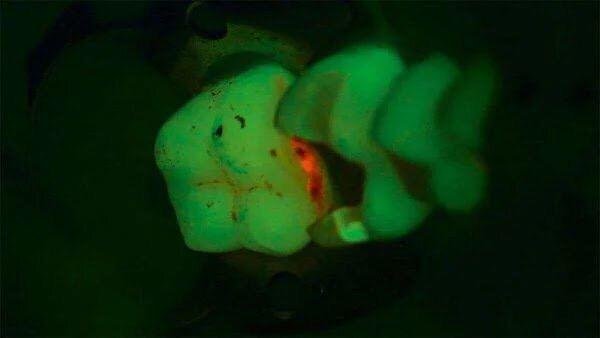

Микроскоп даёт возможность смотреть на зуб в разных диапазонах, в том числе в ультрафиолете. Вот тут видны реставрационные материалы. А вот вам пример обычного снимка:

И аналогичный поиск кариеса с окрашивающей подсветкой:

Полезно иметь такое прямо в операционном микроскопе, чтобы не убирать лишние ткани. Это не суперпрорыв, но очень удобно.